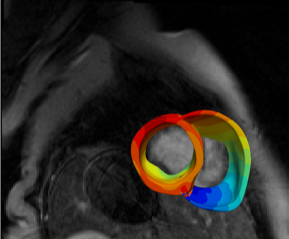

Image, left: A virtual heart model is developed using MRI and PET scans. Bands of colour signify the electrical wave of an irregular heartbeat. Photo courtesy of Professor Natalia Trayanova.

Image, right: A virtual heart is developed using scans of a patient’s heart (blue). Areas where disrupted electrical activity is present (arrhythmia) are represented by yellow and red. Photo courtesy of Professor Natalia Trayanova.